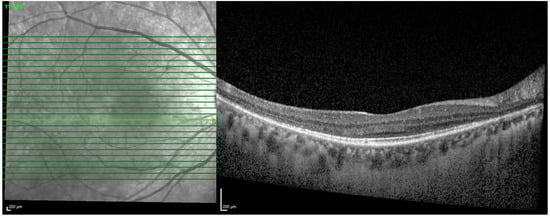

- Ahn, S.J.; Ryu, S.J.; Joung, J.Y.; Lee, B.R. Choroidal Thinning Associated With Hydroxychloroquine Retinopathy. Am. J. Ophthalmol. 2017, 183, 56–64. [Google Scholar] [CrossRef] [PubMed]

- Halouani, S.; Le, H.M.; Querques, G.; Borrelli, E.; Sacconi, R.; Battista, M.; Jung, C.; Souied, E.H.; Miere, A. Choroidal Vascularity Index in Hydroxychloroquine Toxic Retinopathy: A Quantitative Comparative Analysis Using Enhanced Depth Imaging in Spectral Domain Optical Coherence Tomography. Retina 2023, 43, 94–101. [Google Scholar] [CrossRef] [PubMed]

| Choroidal thickness |

|

| Choroidal vascularity index |